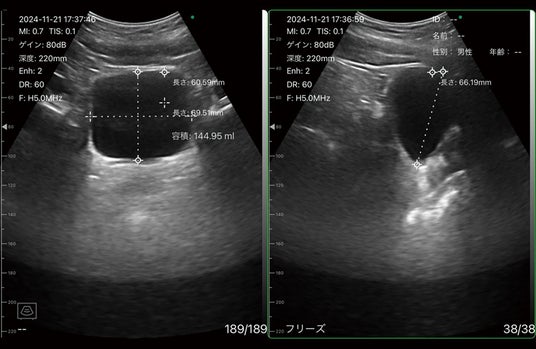

・各種計測・容積計測

▲容積計測機能使用イメージ(膀胱)